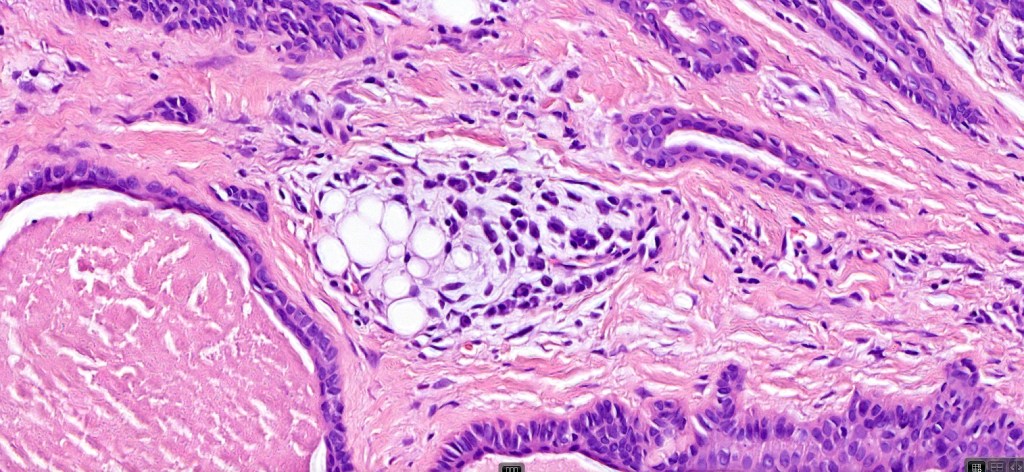

•Well circumscribed unencapsulated, nodular/multinodular silhouette composed of an admixture of epithelial & mesenchymal elements

•Mixed epithelial component including nests & cords of epithelium with abundant, eosinophilic cytoplasm & small vesicular nuclei

•Clear cell change

•Glandular differentiation sometimes showing apocrine differentiation

•Myoepithelial layer in glandular foci

•Plasmacytoid myoepithelial cells; clear cell change

•Follicular & sebaceous differentiation

•Keratocysts & squamous foci

•Myxoid change

•Chondroid foci

•Fat (lipomatous mixed tumor)